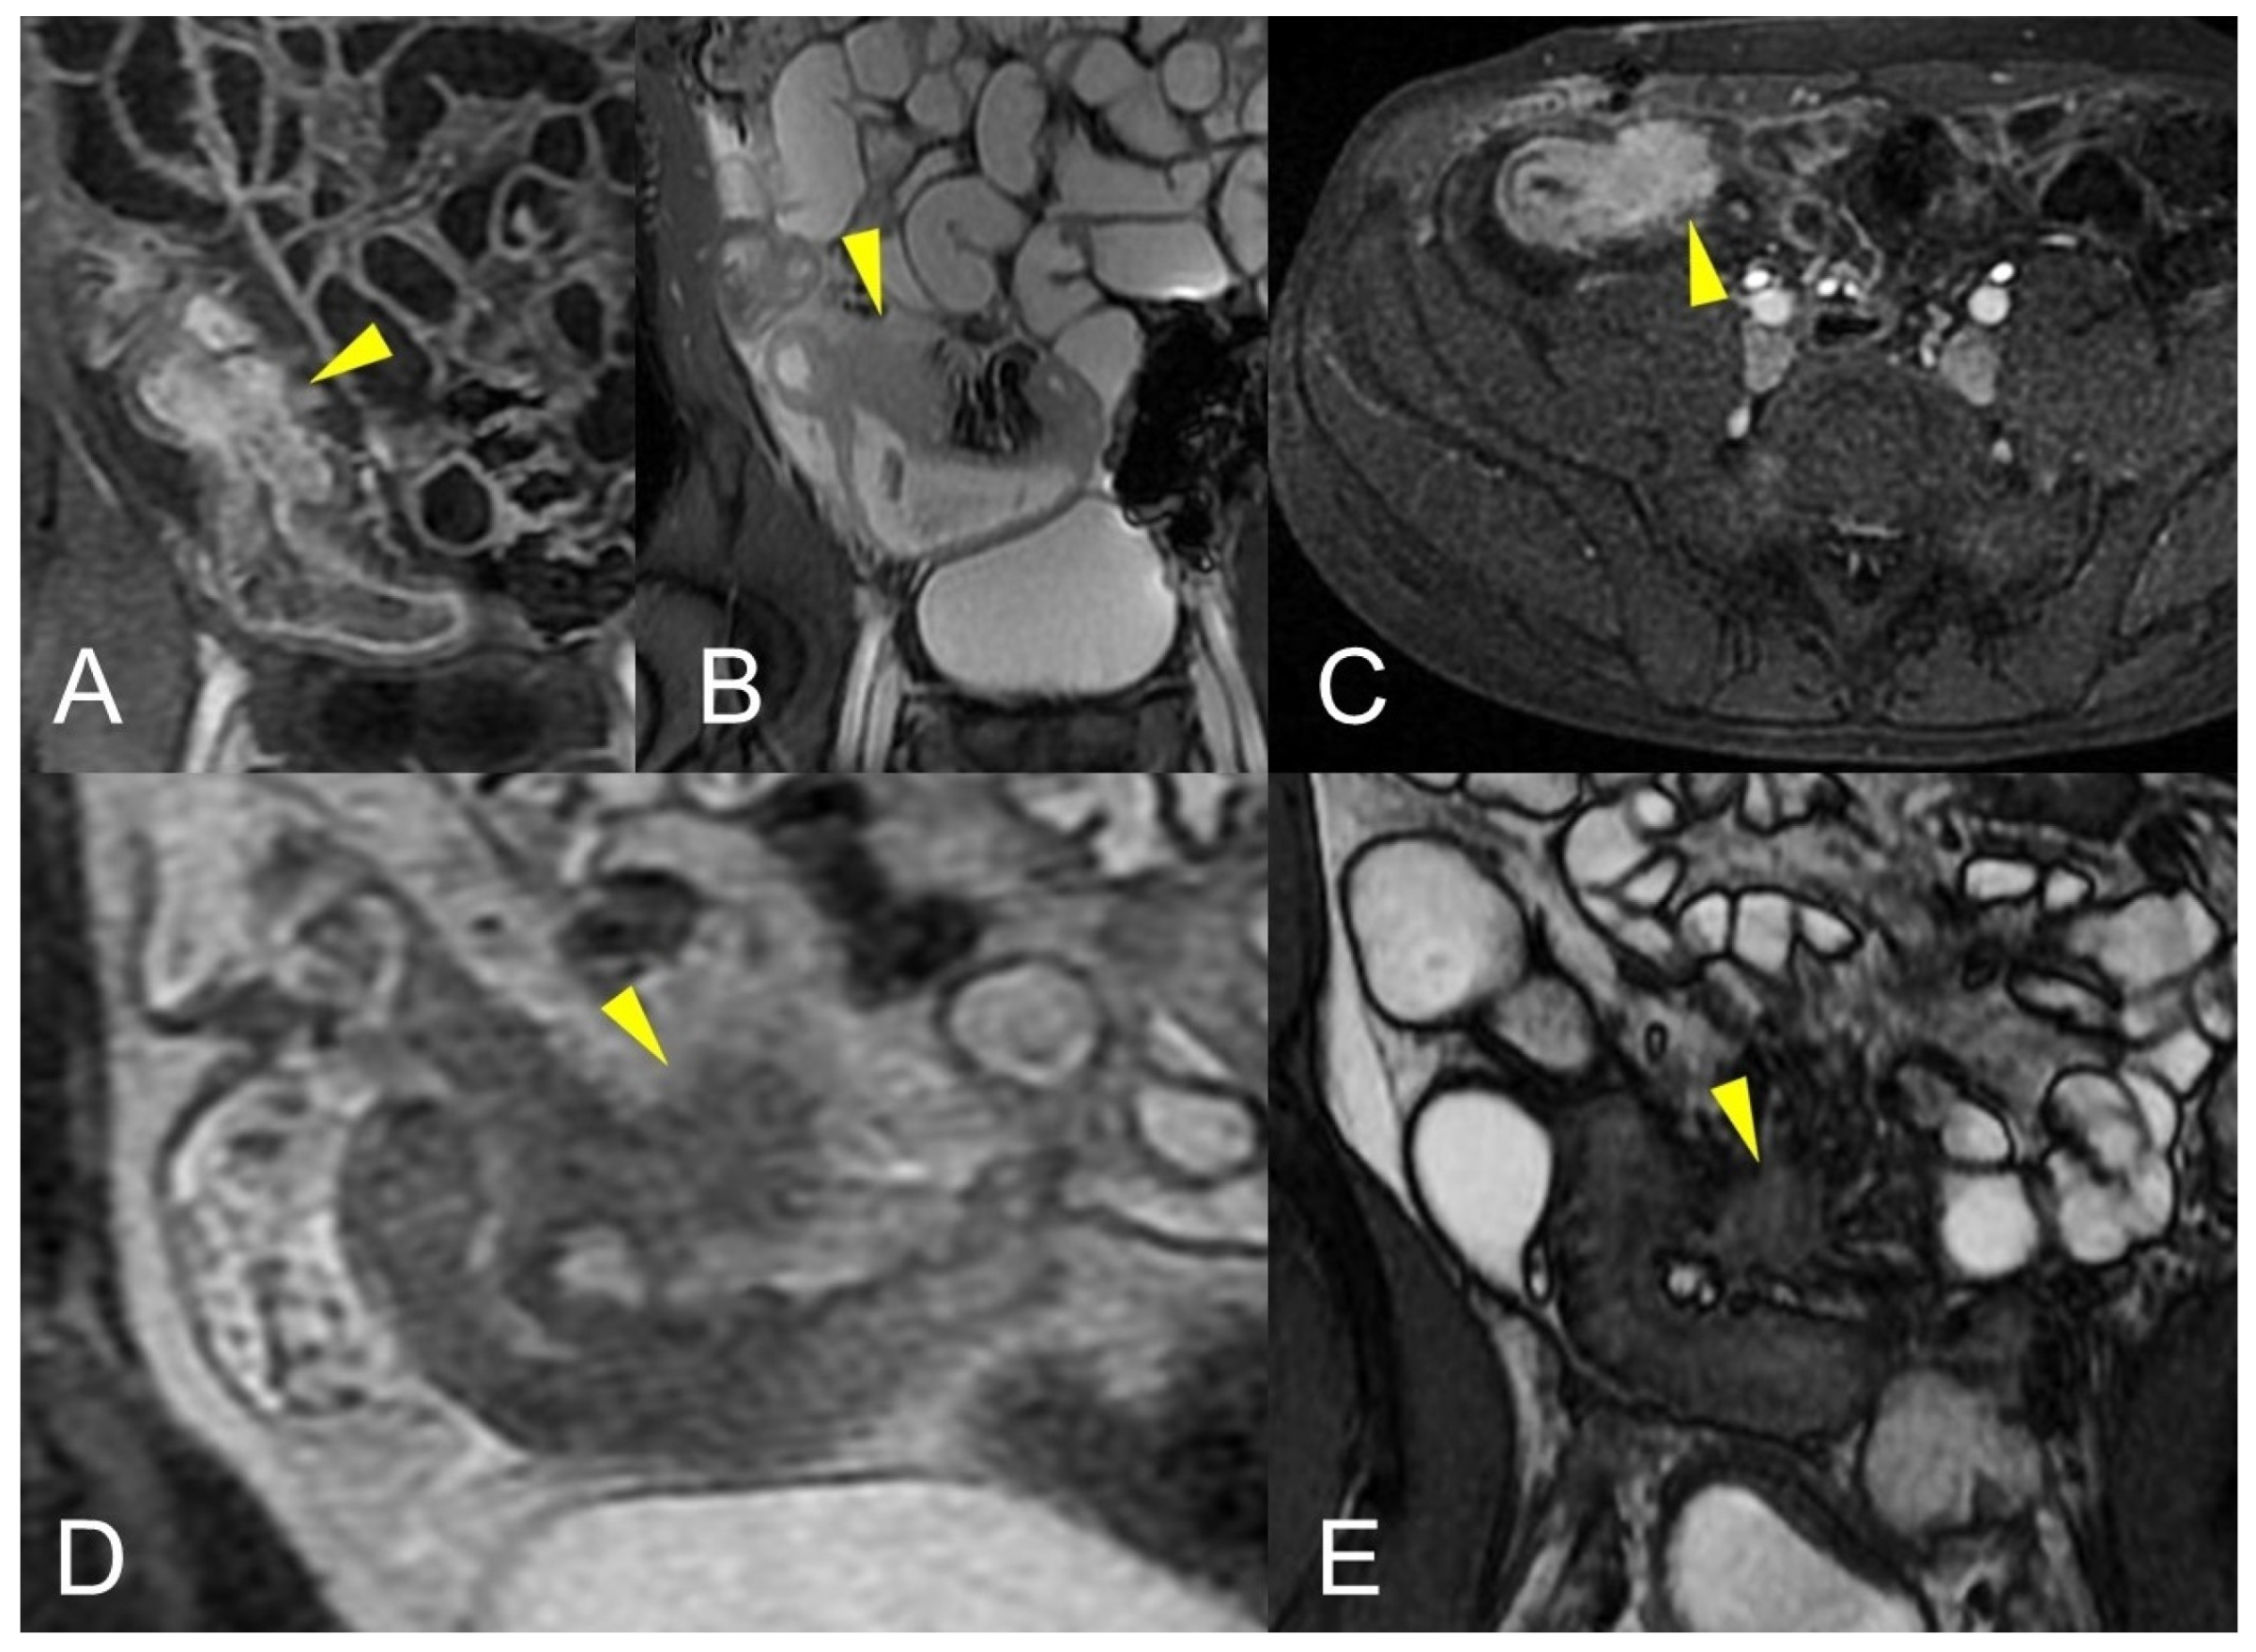

Figure 12.

Inflammatory conglomerate represents a climbing mesenteric fat involvement in the context of penetrating disease and mesenteric inflammation. The components of the fistulas within the mass can be difficult to detect because it often coexists with phenomena of retraction that are expressed on the intestinal loops nearby or on the ureters. Small inflammatory conglomerate in the context of the mesentery adherent to a segment of the pathological small intestine, with active disease (yellow arrowheads in (A,C): coronal (A) and axial (C) contrast-enhanced fat-suppressed T1-weighted image and in (B,E) (coronal fast imaging employing steady-state acquisition; FIESTA image) and (D) (coronal T2-weighted MRE image)).

Figure 13.

Two different patients with, respectively, an inflammatory conglomerate (Patient 1) of medium size (yellow arrowheads in (A–C)) and of large size (green arrowheads in (D–F)) (Patient 2). Coronal (A,B) and axial (C) fast imaging employing steady-state acquisition (FIESTA) image. Coronal FIESTA image (D) and coronal without (E) and with (F) contrast-enhanced fat-suppressed T1-weighted image. Notably intense contrast enhancement in (F) image underlines the significant state of inflammation of the disease in the active and complicated phase.